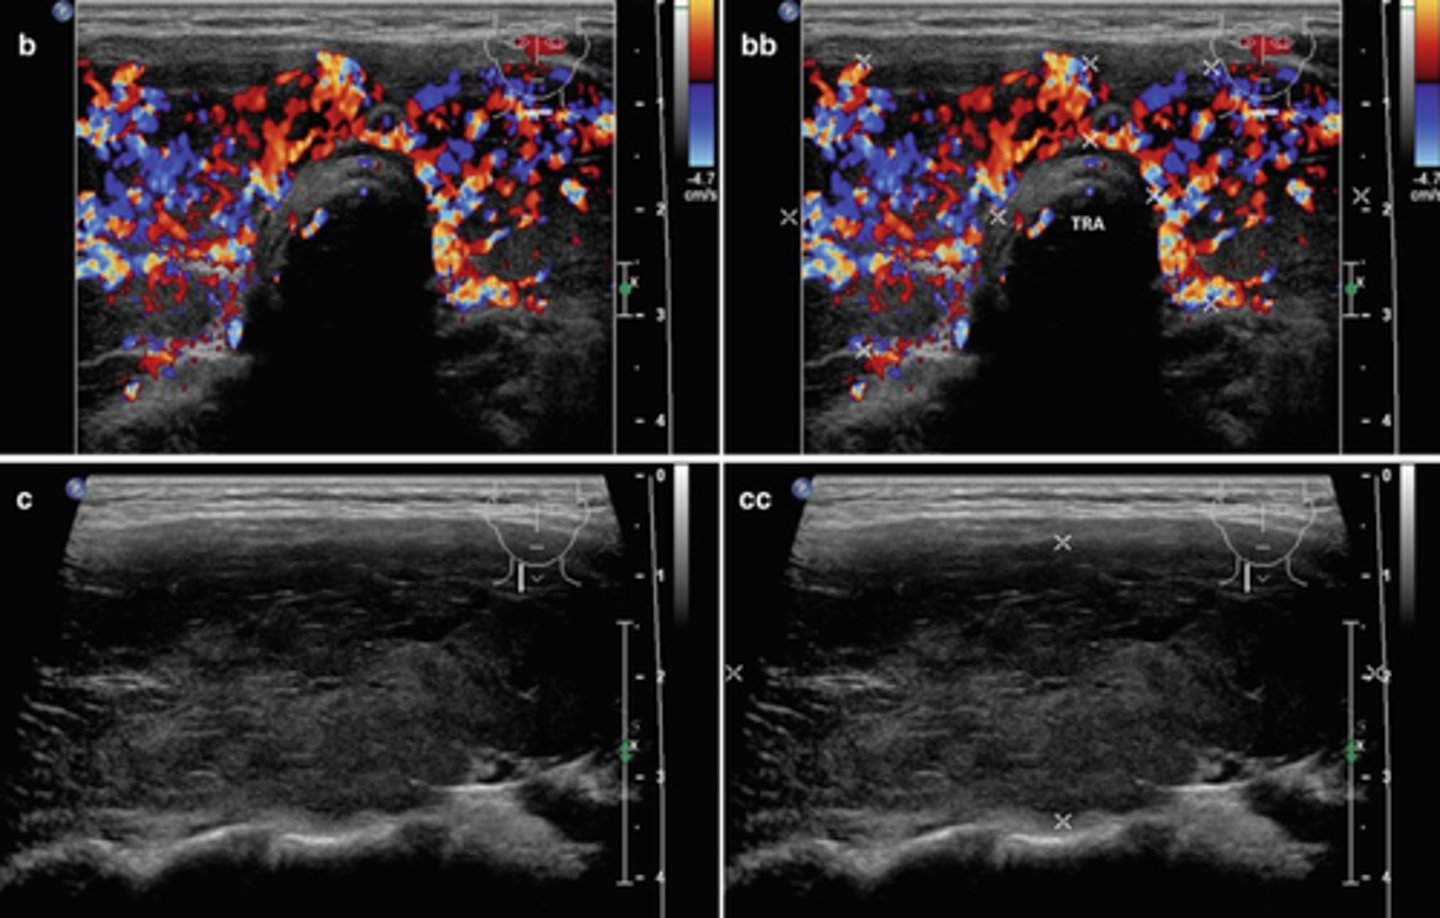

Benign Thyroid Neoplasms - Adenoma:

Etiology

-Composed of _____ tissue

-____ common thyroid neoplasm

Clinical findings

-Asymptomatic

-_____

-_____ prevalence (7:1)

Sonographic findings

-Homogeneous _____ mass

-Prominent _____echoic peripheral halo

-_____ blood flow

-May degenerate and appear _____

-"_____" nodule on nuclear medicine scan

-Composed of epithelial tissue

-Most common thyroid neoplasm

-Hyperthyroidism

-Female prevalence (7:1)

-Homogeneous echogenic mass

-Prominent hypoechoic peripheral halo

-Peripheral blood flow

-May degenerate and appear complex

-"Cold" nodule on nuclear medicine scan